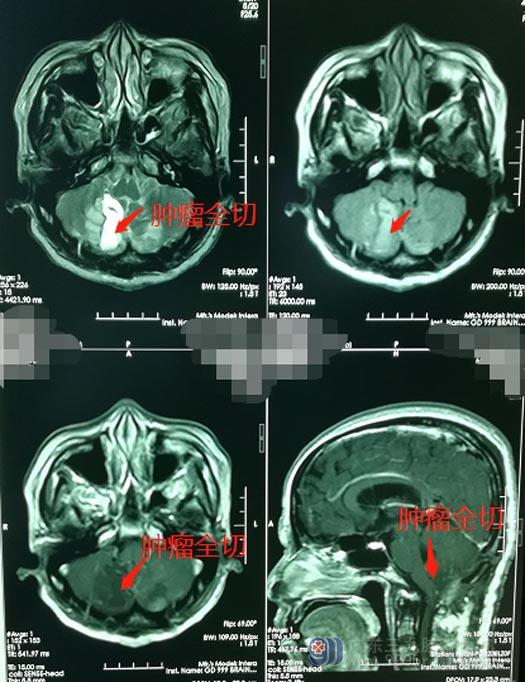

终于看到黄阿姨安全地推出了手术室,肿瘤被完整地切除,术前所担心的并发症都没有发生,家人终于都松了口气。术后病理回报:淀粉样小体伴周围胶质细胞增生,出院回家后,黄阿姨还需要定期返院复查。

▲手术后